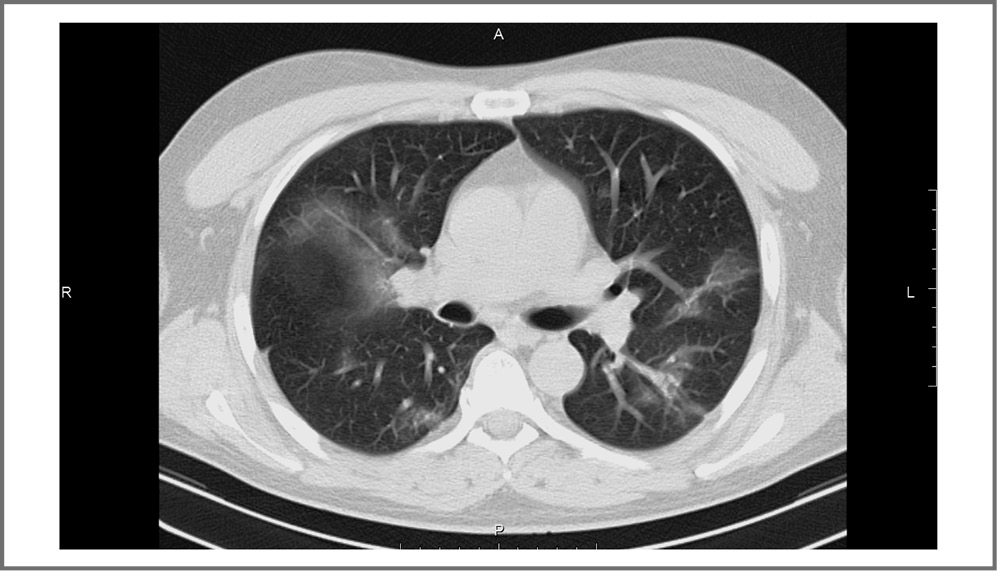

Мужчина, 41 год, 06.10.2021 отметил повышение температуры тела до 39,0°С, появление приступообразного сухого кашля, потерю обоняния. На момент госпитализации имел сопутствующее заболевание – сахарный диабет 1-го типа. Ему 06.10.2021 выполнена спиральная компьютерная томография (СКТ) органов грудной полости (ОГП), по данным которой выявлены двусторонние фокусы «матового стекла», признаки вирусной пневмонии, объем поражения ~25% (рис. 2). Получен положительный результат ПЦР-мазка из зева на РНК SARS-CoV-2 от 06.10.2021.

Рис. 2. Компьютерная томограмма ОГП на уровне бифуркации трахеи от 06.10.2021. КТ-картина двусторонней полисегментарной вирусной пневмонии, объем поражения ~25%.

Fig. 2. CT scan of the chest organs at the level of the tracheal bifurcation from 06.10.2021. CT picture of bilateral polysegmental viral pneumonia, lesion volume ~25%.